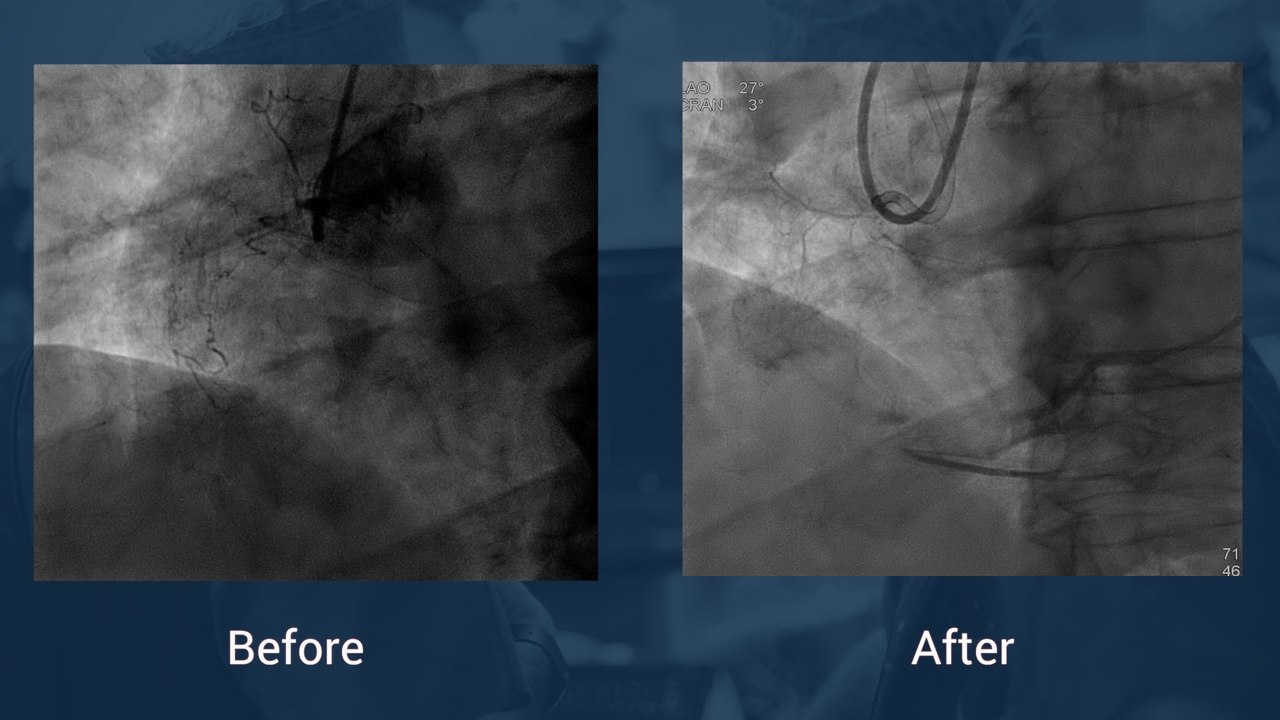

Short calcified proximal SFA lesion